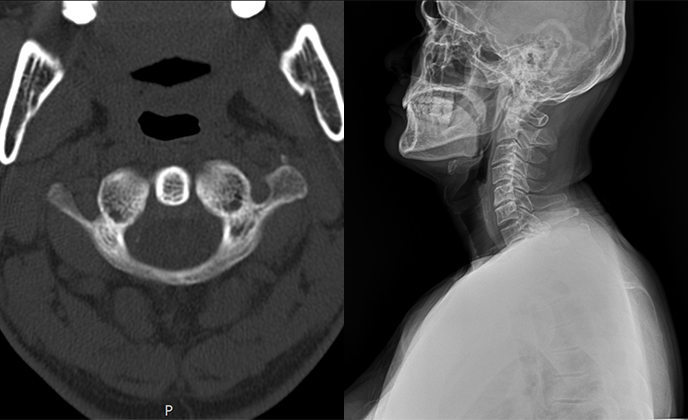

체형교정, 족부교정, 턱관절교정, 턱관절 난치성 질환, 근골격계통증, 척추관절질환, 추나요법, 약침, 한방내과

척추관절질환, 교통사고후유증, 턱관절난치병, 화병, 소화기질환, 안면마비